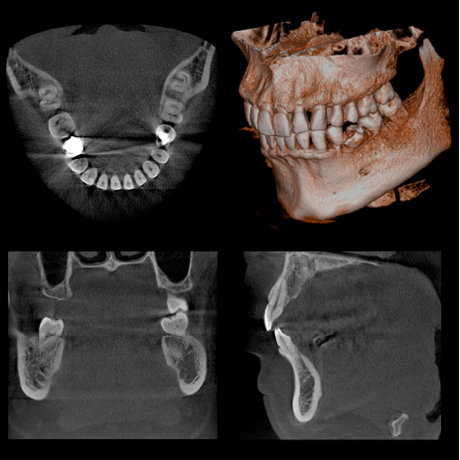

最先端のデジタルテクノロジーを駆使し、より少ないX線で高解像度な画像が得られる、CT撮影、パノラマ撮影が可能なレントゲン装置です。

さらに洗練された多彩な画像処理により、多角的な診査を行うことが出来ますので、的確な診断を行う上で重要な役割を担っています。

φ40×H40mmの局所領域から、全歯列対応のφ100×H80mmまで鮮鋭なCT画像が撮影可能です。

根管治療、歯周病、親知らず、インプラント、上顎洞、顎関節などの治療においてより正確な診査、診断が行えます。

CT撮影画像